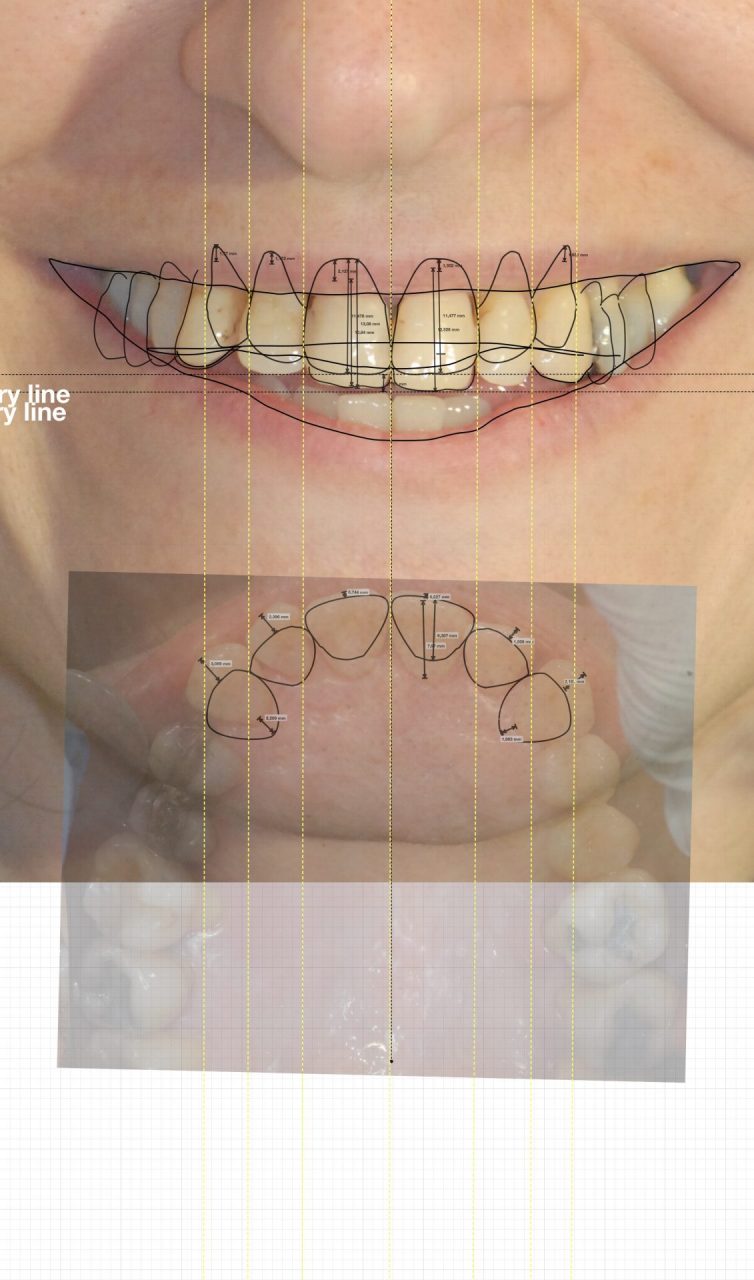

8 – Cos’è il Digital Smile Design?

«Un software che permette di progettare in digitale la riabilitazione estetica e funzionale del sorriso. Strumenti semplici ed automatici mediante un percorso guidato ed intuitivo presentano al paziente l’anteprima del risultato protesico. L’odontotecnico, d’atra parte, acquisisce tutte le informazioni necessarie per l’esecuzione del lavoro. Tutto ciò nell’ambito di trattamenti di odontoiatria estetica che prevedono terapie protesiche, conservative, ortodontiche e implantari. L’obiettivo del dentista dovrebbe sempre essere l’ottenimento, oltre che di una funzione e di una biologia ottimali, anche di un aspetto estetico gradevole».

L’analisi digitale del sorriso

L’analisi digitale del sorriso